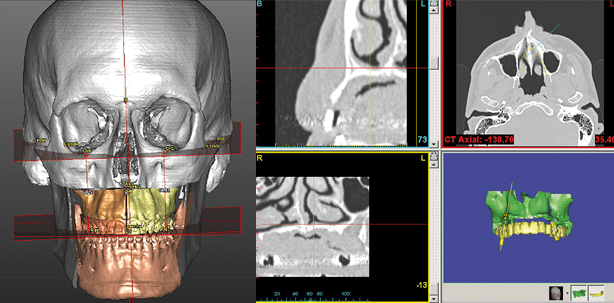

Durch die Möglichkeit bildgebende Verfahren wie das CT oder DVT digital aufnehmen zu können, können diese Datensätze mit speziellen Software-Programmen dreidimensional aufbereitet werden. Hierdurch soll eine exakte Planung z.B. von Operationen im MKG-Bereich ermöglicht werden. Allerdings werden solche modernen Verfahren bisher nur von wenigen umfassend genutzt. Anhand von Fallbeispielen wird daher die umfangreiche Erfahrung mit der konsequenten 3-D-Datengewinnung, 3-D-Planung, Umsetzung und Insertion mittels 3-D-Schablone von dentalen Implantaten vermittelt. Außerdem werden die Möglichkeiten des Einsatzes von 3-D-Verfahren zur Planung und Umsetzung von Dysgnathie und craniofacialen Operationen verdeutlicht, die spezielle Software voraussetzen. Die Indikationen und die Vor- und Nachteile der Verfahren werden dargestellt.

Für die 3-D-Planung von Dysgnathieoperationen sind zunächst die Herstellung von Ober- und Unterkiefermodellen (oder die digitale Abdrucknahme) und die Bestimmung der Bisslage sowie extraorale Fotos oder Weichteilscanner4 notwendig. Nach Scannen der Modelle erfolgen die Herstellung eines Fixierbogens und das CT/DVT des Gesichtsschädels. Die DICOM-Daten werden konvertiert und die Modelle mit den Daten gematcht. Die Verlagerung der Kiefer kann in allen Raumebenen für den Ober- und Unterkiefer sowie das Kinn vorgenommen und die Verlagerungsstrecken abgelesen werden. Durch Überlagerung mit den extraoralen Fotos/Scans kann die Weichteilveränderung simuliert werden, dem Patienten diese gezeigt und durch ihn genehmigt werden. Abschließend werden die Operationssplinte bestellt.

Die 3-D-Planung von craniofacialen Operationen setzt ein CT des Schädels voraus. Diese DICOM-Daten werden dann mit der Software SimPlant 16.0 verarbeitet. Je nach notwendiger OP werden zunächst Hilfslinien zur Herstellung der Symmetrie angelegt, um so genau die Ursache der Fehlbildung beurteilen zu können und auch gleichzeitig die OP mit den Verlagerungsstrecken geplant werden. Auch hier kann nach Genehmigung durch den Patienten/Eltern ein Splint angefertigt werden.